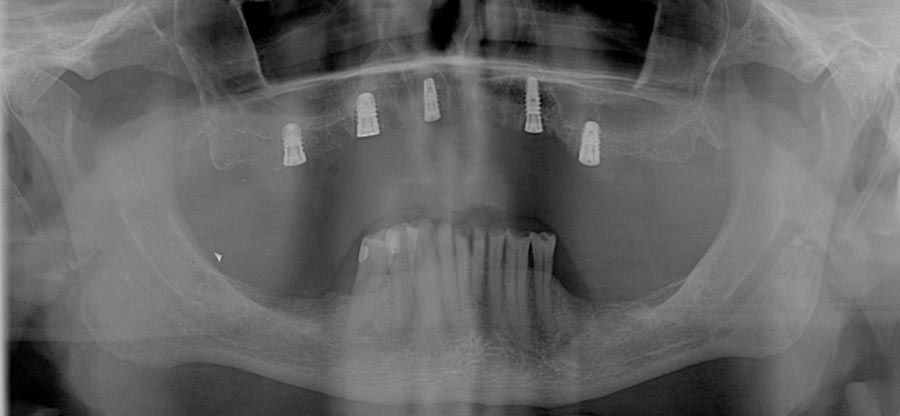

After many years of postponing, the time had come for this patient to fix his teeth. He elected to start on the upper and move to the lower one year later.

Occlusal (mirror) view of the upper implants. This patient had good bone in these five areas. If the bone was better we would have added a sixth implant.